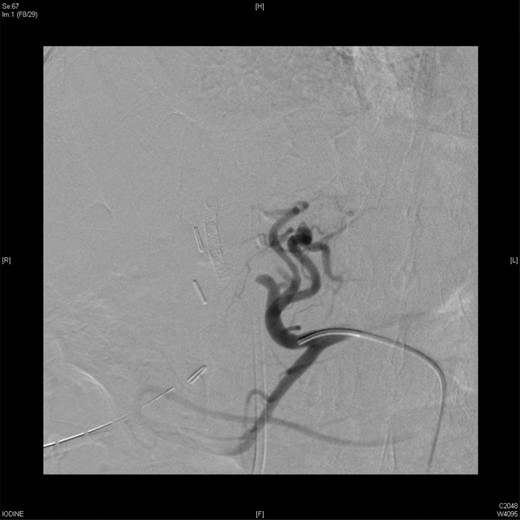

On Day 7, the patient bled again from the same aneurysm of the left hepatic artery. A repeated angiography revealed the bleeding with a reduced flow in the stented, replaced right hepatic artery (Fig. 4). The active bleeding was stopped using gel-foam embolization of the two branches of the left hepatic artery (Fig. 5) with a decision to embolize the whole left hepatic artery if bleeding did not stop while holding the heparin infusion. The patient's liver function was preserved, and the bleeding stopped despite anticoagulation.

An angiographic scan showed reduced flow in the stented replaced right hepatic artery.